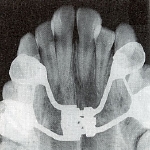

拡大前X線像

拡大前X線像 拡大直後のX線像

拡大直後のX線像 拡大後半年後のX線像

拡大後半年後のX線像

X線像

1か月で6mmほど拡大したため、急速な拡大に骨の新生が追いつかないため、拡大直後の正中縫合はまだ骨が出来ていません。そのためX線像では正中部が透過像となり黒く抜けていることが分かります。その後、約半年かけて、正中部に新しい骨が出来ると、新しい癒合部が出来ます。つまりその分だけ、上顎骨の横幅が拡大したことになります。